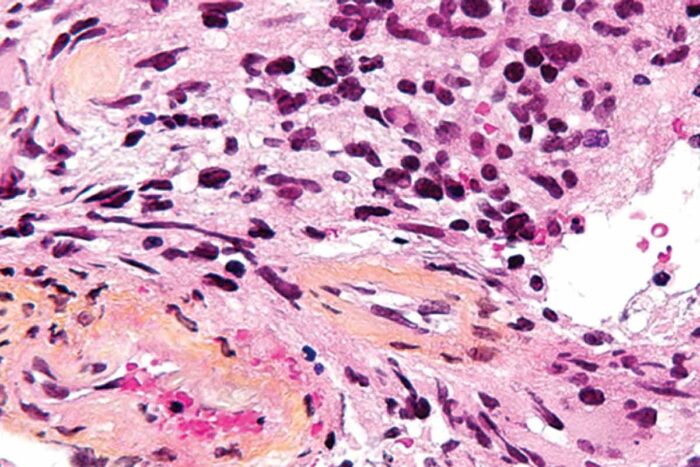

Why is cancer more common in men than women?